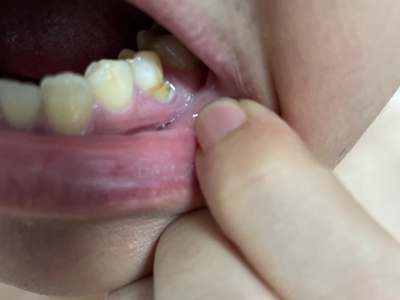

楔状缺损症状图片

楔状缺损是一种非龋性牙颈部慢性损伤,是指发生在牙齿唇、颊面颈部的慢性硬组织缺损。典型缺损由两个夹面组成,口大底小,呈楔形。楔状缺损多发生于中老年人,主要原因是刷牙不当,防治措施是调整咬合关系,改善刷牙方法,配合相应的治疗。

楔状缺损与年龄相关,即年龄越大,缺损越重,患者多有横刷牙习惯,患牙为多颗甚至全口,常以口角附近的牙齿(尖牙、前磨牙)为重。典型表现为牙颈部缺损,呈楔形,由两个夹面组成,口大底小,缺损处质地坚硬,表面光滑,边缘整齐,无染色,轻微泛黄常为牙齿本色,严重时可导致牙髓腔暴露甚至牙齿横向折断,根据缺损深浅不同,可伴有牙齿敏感甚至疼痛。